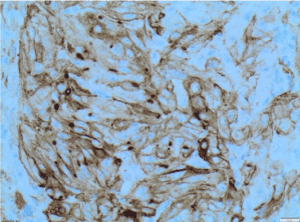

Histological features and immunoprofile of metastatic high grade sarcomatous renal carcinoma of left supraclavicular lymph node were depicted in Figures 4-11.

Figure 9. Vimentin X200 immunohistochemistry-Tumour cells are positive for vimentin X200